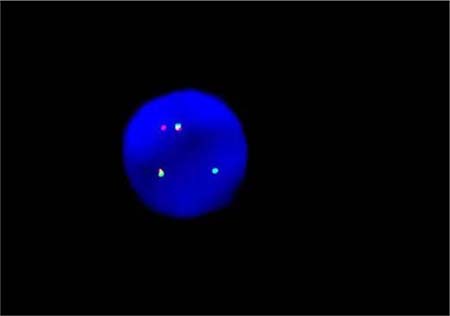

By fluorogenic quantitative PCR, centrifugation of sampled bone marrow or blood, which ACK Lysis Buffer had been added into, was conducted. Then, DNAs were extracted to be amplified. After adding samples according to the amplification system, each amplification sequence was operated in corresponding reaction conditions. The probe used for ETO genes is: Vysis LSI RUNX1/RUNXITI Dual Color, Dual Fusion Translocation Probe (Model: 08L70–020), probe map (see Figure 2). Metasystems ISIS software was applied to signal analysis. The principle of cell counting is: within a nucleus, if the distance between two signals is less than the diameter of one signal with obviously visible yellow by superposition of red and green, they can be regarded as fusion signals. Points for attention: ①. Selected cell nuclei should be complete with a clear boundary and a proper size and without fragmentation or overlapping. ②. Signals of selected cell nuclei should be bright and analysis of cells with excessively dispersed signals should be avoided. ③. By regular movement of lens (up, down, left and right), each analyzable cell should be analyzed without arbitrary omission. ④. Signal patterns of nuclei should be recorded and proportions of cells of each signal pattern to total cells should be figured out. ⑤. Detection results should be evaluated according to CUTOFF value of each positive signal pattern established by this laboratory. ⑥. After analysis of 200 cell nuclei, when the outcome is close to CUTOFF value, counting cells should be increased to 500. The normal ETO diagram (see Figure 3) and the ETO fusion diagram (see Figure 4) by fluorogenic quantitative PCR.

Figure 4: The ETO fusion diagram of PCR testing.